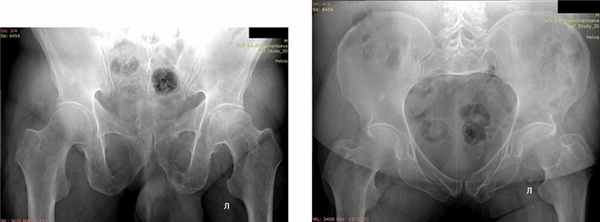

Отдаленные результаты через 12 мес: на контрольных рентгенограммах определялись консолидированные переломы боковых масс крестца справа, седалищной кости справа (рис. 2). Рис. 2. Пациентка, Р. 68 лет. Рентгенография консолидированного перелома боковой массы крестца справа через 12 мес после операции. Остеосинтез канюлированным винтом. Консолидированный перелом седалищной кости справа. а — проекция: выход из таза; б — проекция: вход в таз. По шкале S. Majeed — 85 баллов, по тесту «Timed up & go» [30] 9 с (рис. 3). Рис. 3. Пациентка Р., 68 лет. а–в — внешний вид и функция через 12 мес после операции.

Отдаленные результаты через 12 мес: на контрольных рентгенограммах определялись консолидированный перелом лонной кости, ложный сустав ветви седалищной кости (рис. 4). Рис. 4. Пациент Л., 70 лет. Контрольные рентгенограммы через 12 мес. Консолидированный перелом лонной кости, ложный сустав ветви седалищной кости. а — проекция: выход из таза; б — проекция: вход в таз. По шкале S. Majeed — 82 балла, по тесту «Timed up & go» теста 11 с.